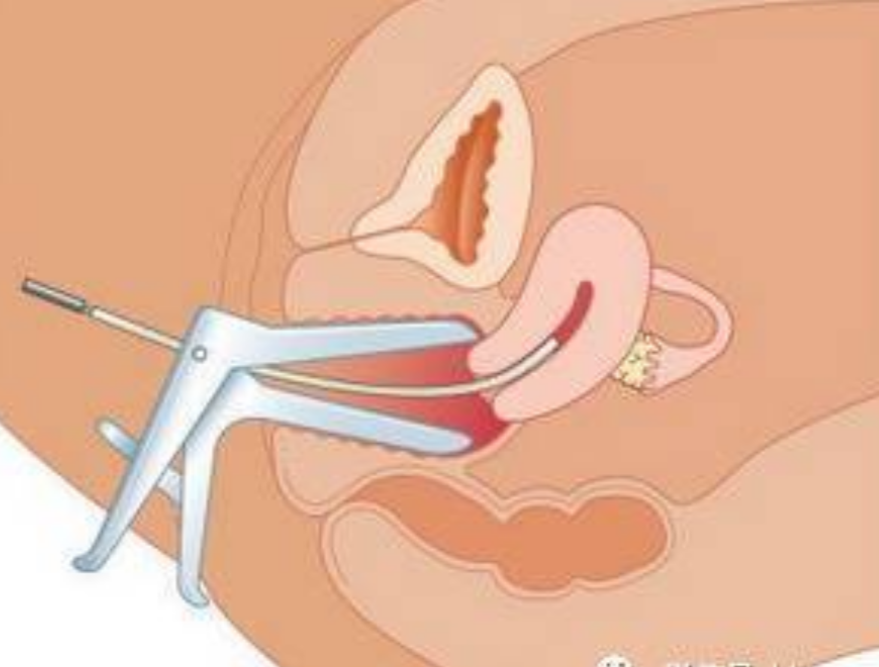

人工陰道治療中的

人工陰道作用

人工陰道治療

人工陰道治療前期

人工陰道治療前後

A:原發性陰道鱗狀上皮癌對放療比較敏感,可採用腔內鐳療、體外照射或放射性同位素局部應用等治療。一般早期陰道癌以腔內照射為主,放射源主要為鐳及鈷,現在多用銫,利用陰道容器,裝配不同劑量及放置不同時間。體外照射治療時放射量由主治醫師根據患者情況具體……